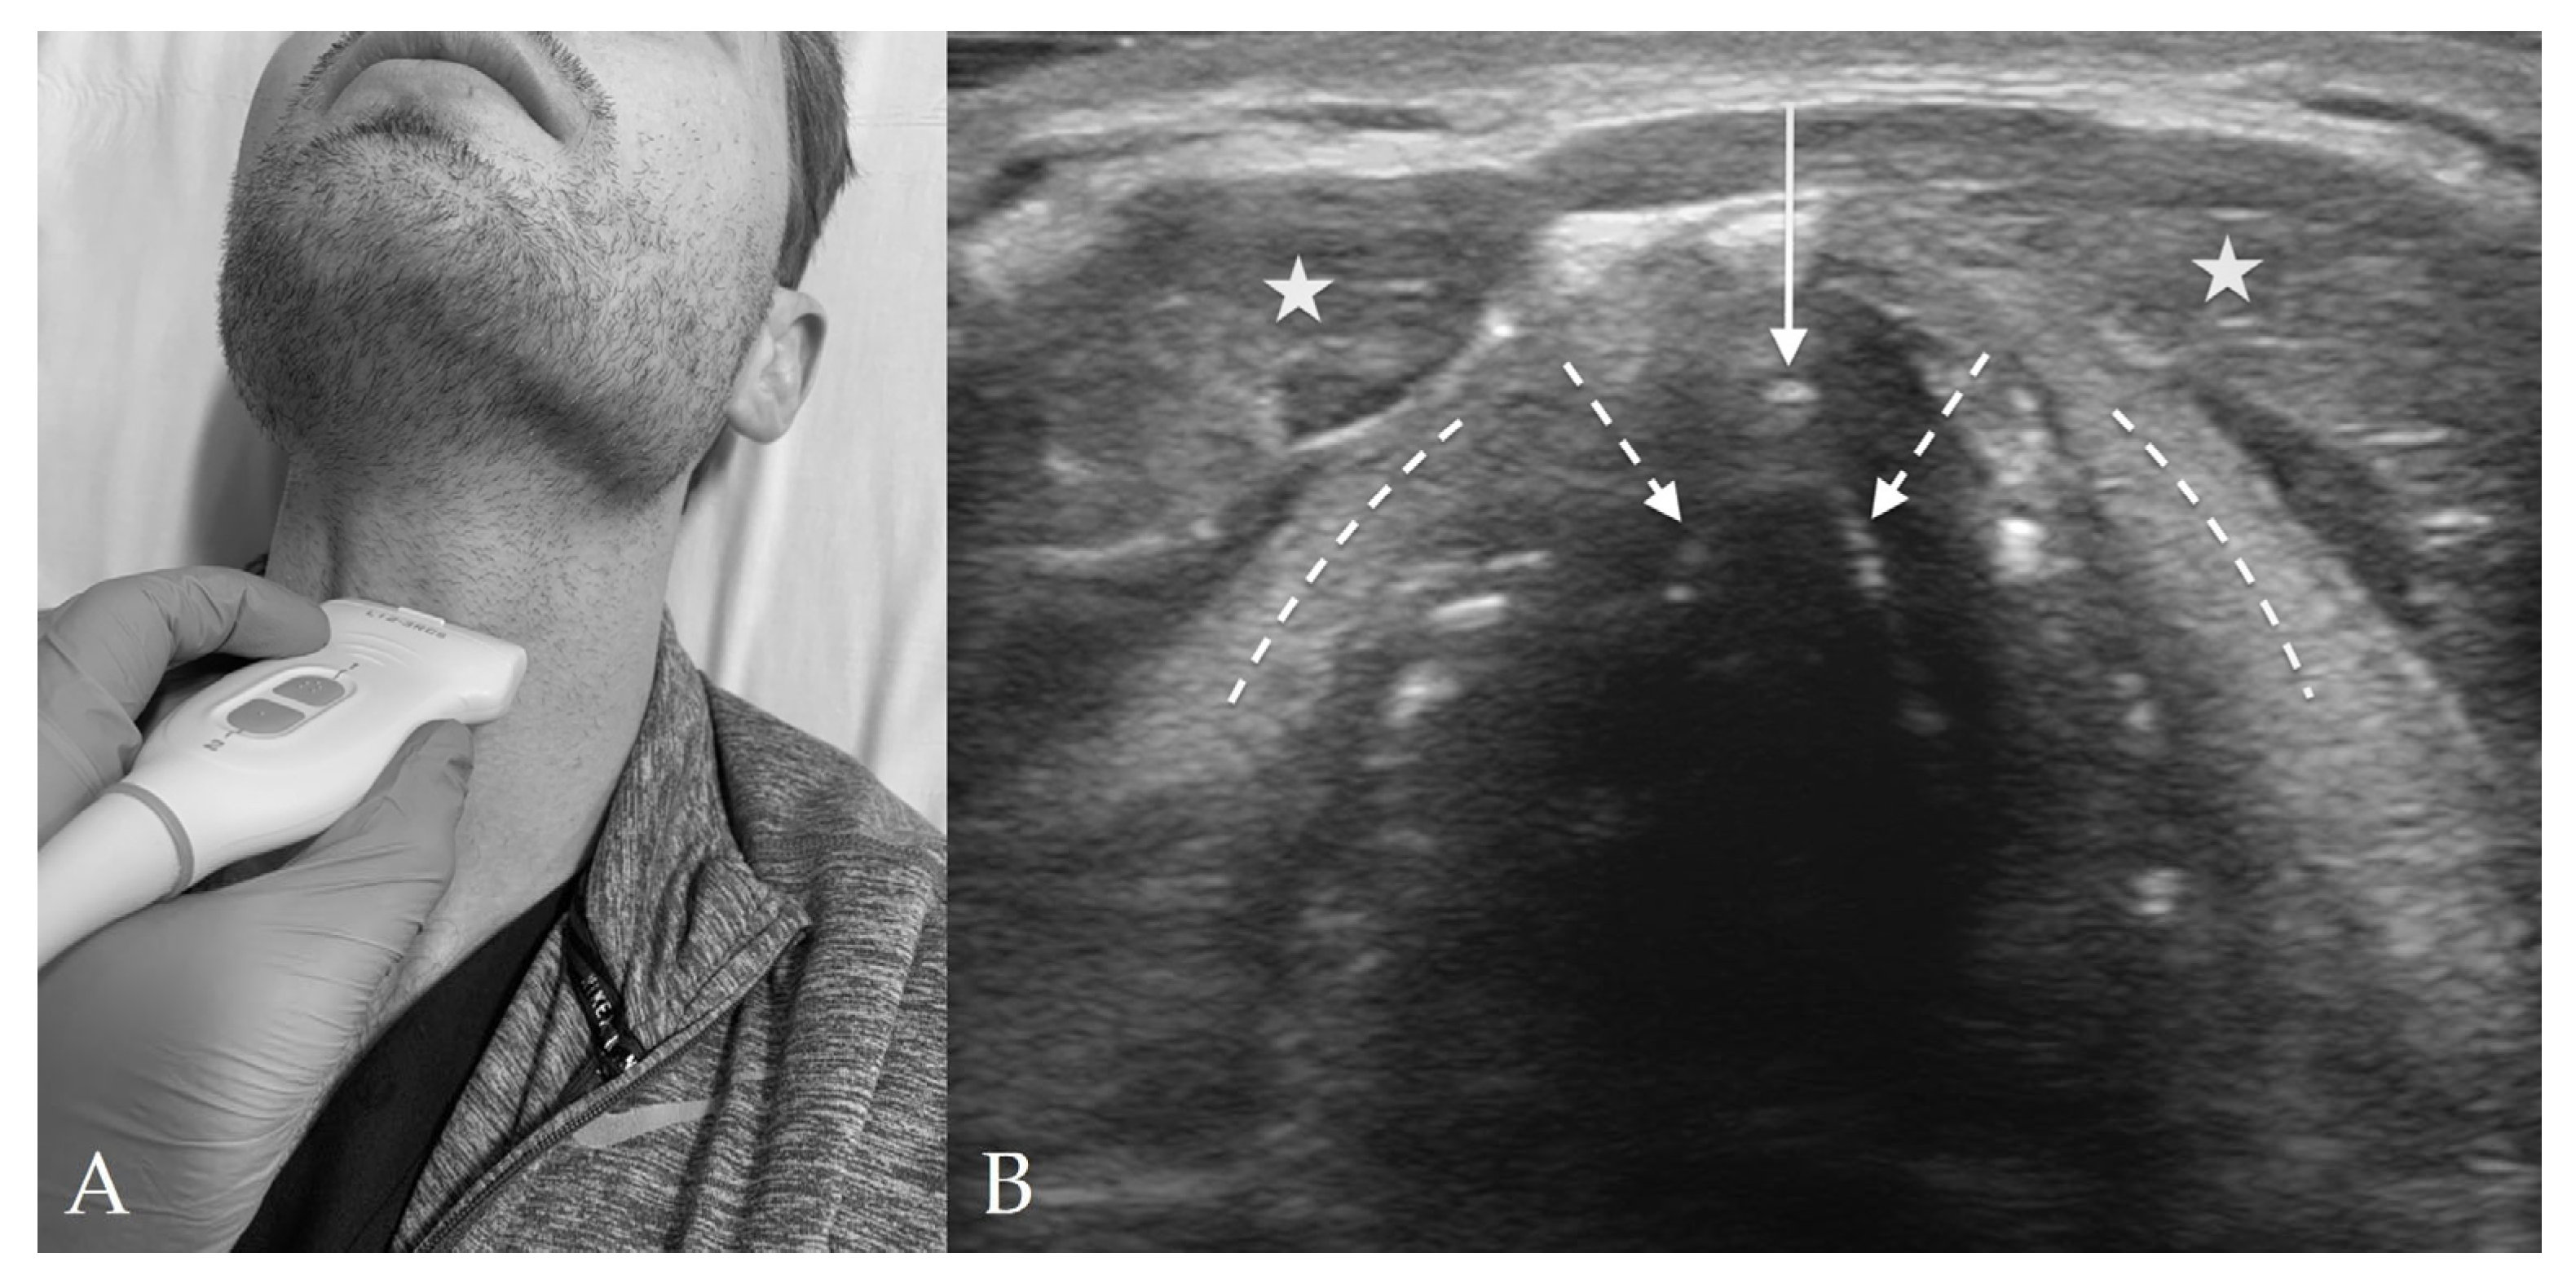

4.3. Thyroid View